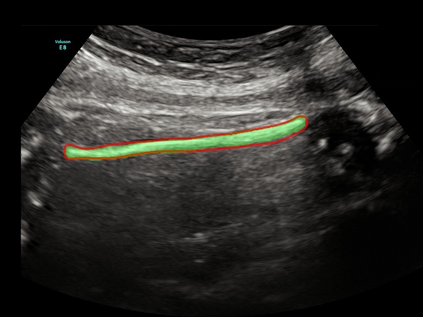

In this paper, we propose an end-to-end multi-task neural network called FetalNet with an attention mechanism and stacked module for spatio-temporal fetal ultrasound scan video analysis. Fetal biometric measurement is a standard examination during pregnancy used for the fetus growth monitoring and estimation of gestational age and fetal weight. The main goal in fetal ultrasound scan video analysis is to find proper standard planes to measure the fetal head, abdomen and femur. Due to natural high speckle noise and shadows in ultrasound data, medical expertise and sonographic experience are required to find the appropriate acquisition plane and perform accurate measurements of the fetus. In addition, existing computer-aided methods for fetal US biometric measurement address only one single image frame without considering temporal features. To address these shortcomings, we propose an end-to-end multi-task neural network for spatio-temporal ultrasound scan video analysis to simultaneously localize, classify and measure the fetal body parts. We propose a new encoder-decoder segmentation architecture that incorporates a classification branch. Additionally, we employ an attention mechanism with a stacked module to learn salient maps to suppress irrelevant US regions and efficient scan plane localization. We trained on the fetal ultrasound video comes from routine examinations of 700 different patients. Our method called FetalNet outperforms existing state-of-the-art methods in both classification and segmentation in fetal ultrasound video recordings.